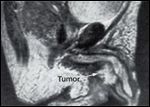

Magnetic Resonance Imaging (MRI) of a Male Urethral Cancer

Work-up of a male with suspected urethral cancer includes cystourethroscopy, CT scan of the abdomen and pelvis, chest x-ray, and retrogradeurography. An MRI scan is useful in evaluating the extent of local disease (Figure 8).